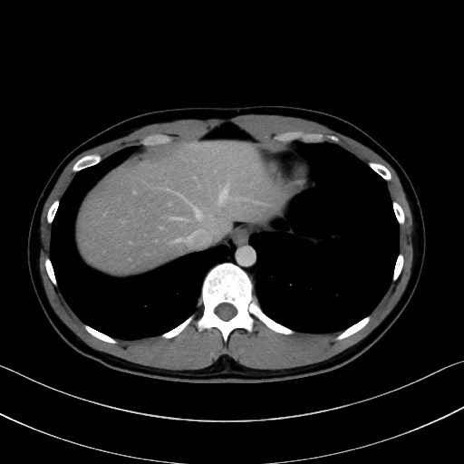

広背筋 (Latissimus dorsi)